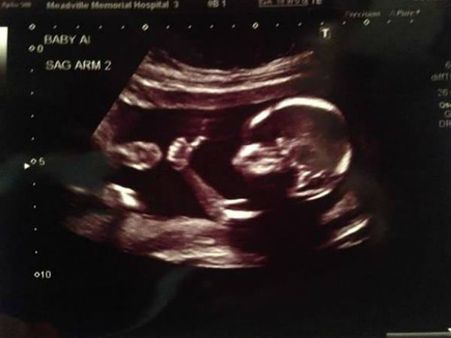

She Was Aborted In Her 3rd Trimester…

Melissa Ohden's mum decided to wash away her pregnancy when she was in her 3rd trimester. She apparently went through saline treatment for 5 long days before she gave birth to Melissa. She turned away her face, as she could not see her child being aborted.

When Melissa was born, she was put in a bucket of saline in the backyard of the hospital, where the foetus that have survived the abortion are let to die a slow death in the buckets filled with saline. She was lucky, as 2 nurses picked her up and rushed her to the emergency room, where doctors saved Melissa's life, even though she had severe respiratory and liver problems. She even had seizures, but Melissa was a fighter.